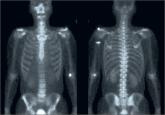

We report a case of asymptomatic intraosseous ganglioneuroma of the ilium, which was initially misdiagnosed as polyostotic fibrous dysplasia. Our...